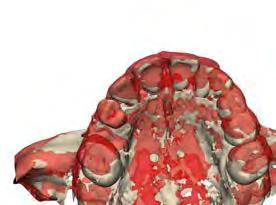

–Tratamiento de un caso de Ortodoncia y Cirugía Ortognática con placas preformadas y tecnología 3D, por la Dra. Elena Bonilla Morente y cols. [62]

–Uso del anclaje esqueletal como alternativa eficiente en el manejo ortopédico de clases III por deficiencia de maxilar superior, por el Dr. Carlos Becerra y cols. [74]

–MARPE, una alternativa a la disyunción en el paciente adulto, por el Dr. Enrique Solano y cols. [88]